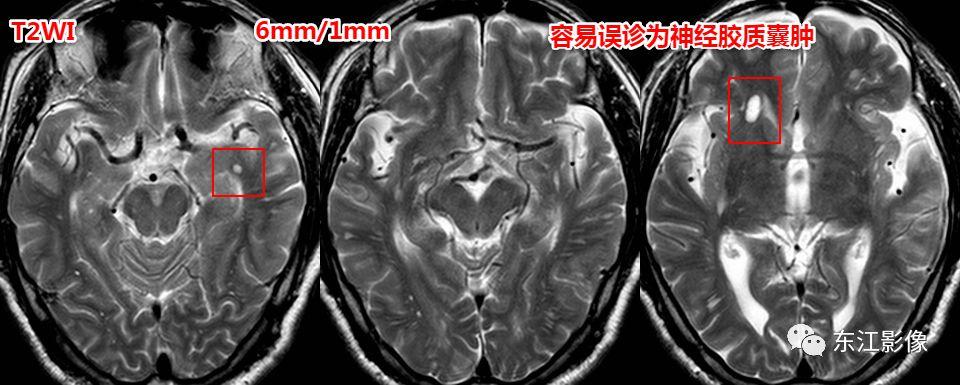

神经胶质囊肿

- 脑实质型神经胶质囊肿罕见,圆形或类圆形,无泪滴状或纺锤样外观;FLAIR边缘多呈稍高信号。

- 神经胶质囊肿多为单发,若多发时,两者之间,扩大的血管周围间隙更为常见。